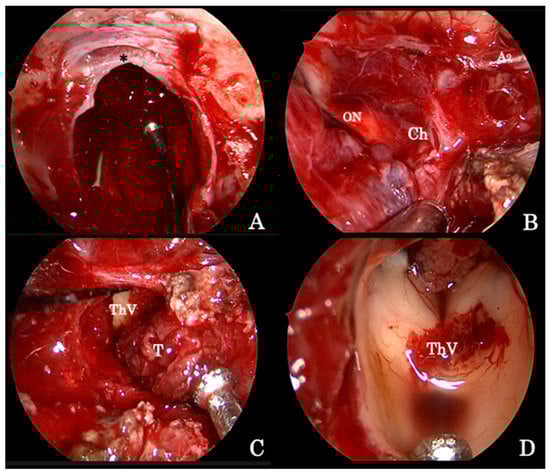

Figure 2. Intraoperative image detailing the endoscopic endonasal procedure for the removal of a giant pituitary adenoma. (A) The osteodural breach is created both at the level of the sella and of the sphenoid planum between the protuberances of the optic nerves; the sellar infradiaphragmatic component of the adenoma is removed first. (B) Thereafter, the supradiaphragmatic area is exposed and tumor removal is completed by means of standard microsurgical techniques taking care of the dissection lesion off the arachnoid under the close-up endoscopic view. (C) The tumor followed along its vertical growth pattern inside the third ventricle cavity, which, at the end, is explored (D). A2 segment of the left anterior cerebral artery (A2); optic nerve (ON); optic chiasm (Ch); third ventricle cavity (ThV); tumor (T); diaphragma sellae (*).

The opening and the exposure of a giant pituitary adenoma extending in the suprasellar supradiaphragmatic space (Figure 1A–C) [23] requires additional bone removal of the tuberculum sellae and of the sphenoid planum between the protuberances of the optic nerves (Figure 2A).

The endoscopic technique has improved visualization, allowing wider exposition of the suprasellar subchiasmatic area and its vascularization; care must be taken, especially for the small branches of the superior hypophyseal arteries that are often displaced by the tumor (Figure 2B), so as to avoid visual field or pituitary function defects [23]. Again, the adenoma removal has to start from the inferior and lateral angles to achieve lesion debulking and to finally dissect the capsule from the neighboring neurovascular structures. When it is not possible to identify a capsule, tumor removal runs gently with the aid of suction, taking care to not injure the tiny vessels encroached by the lesion itself (Figure 2C); at the end, angled scope (30° or 45°) inspections permit one to explore the anatomical details (Figure 2D) and recognize eventual tumor remnants, which are associated with a higher risk of postoperative intralesional hemorrhage.